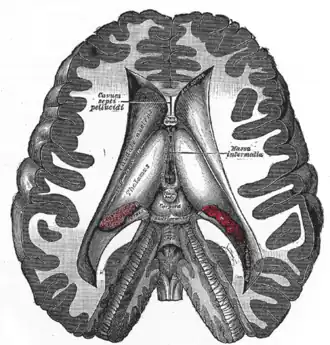

Разрез, показывающий желудочки мозга. Межталамическое сращение показано как massa intermedia в центре справа. | |

Корональный разрез головного мозга человека через промежуточную массу третьего желудочка. | |

Межталамическое сращение (лат. adhesio interthalamica, massa intermedia, commissura mediana, англ. interthalamic adhesion, intermediate mass, middle commissure, в русском языке также известно как межталамическая адгезия, межталамическая спайка, промежуточная масса или срединная комиссура, срединная спайка) — это плоская полоса белого вещества, представляющего собой пучки миелинизированных нервных волокон (пучки аксонов отдельных нейронов), и соединяющая между собой медиальную поверхность обеих половинок таламуса. Медиальные поверхности половинок таламуса образуют верхние части соответствующих боковых стенок третьего желудочка головного мозга. Межталамическое сращение является эволюционно одним из самых древних межполушарных соединений.